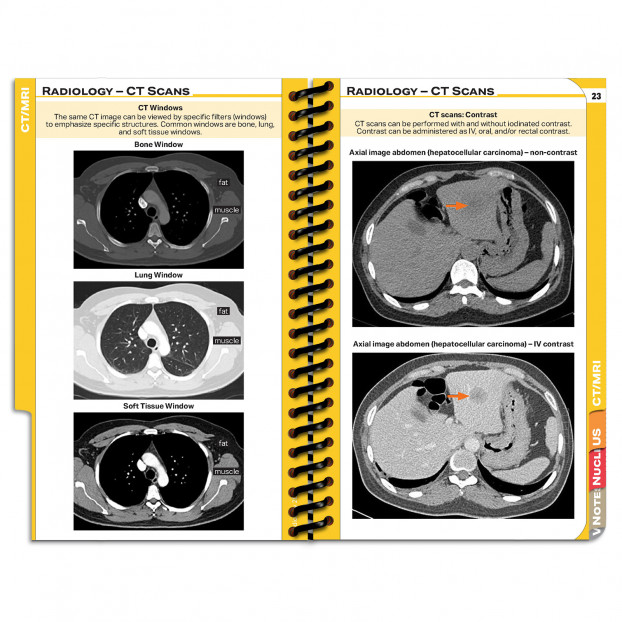

Completely revised and enhanced comprehensive pocket radiology guide covering everything from how to order imaging studies to the most recent American College of Radiology guidelines for management of contrast media allergy and reactions. Chapters cover chest X ray reading, body imaging basics, imaging planes, Hounsfield units, CT scans, MRIs, nuclear medicine study requirements and more. The newly updated ultrasound section includes comparison of ultrasound probe types as well as the FAST and eFAST ultrasound protocols. Each section includes detailed charts to help you select the correct radiologic study and ensure appropriate patient preparation. Patient and provider instructions are attached to each imaging section to guarantee that the test will be ordered and completed successfully (e.g. NPO status, creatinine check, medications to stop taking prior to exam). MDpocket Radiology also includes pretreatment protocols for contrast media reactions, as well as descriptions and treatment guidelines for mild, moderate, and severe contrast reactions from pediatrics to adults. Different CT scans are reviewed including CT windows and representative contrasted and high resolution CT images. The MRI chapter covers multiple MRI sequences (T1, T2, STIR, FLAIR, T2*, DWI, ADC) and includes extensive images that will help you rapidly recognize MRI image types. This guide is designed for use by all healthcare providers in radiology including technicians, radiology departments, imaging technologists, residents, medical students, and more. You can even add other medical information to this guide to have a complete pocket reference guide via our chapter selection tool.